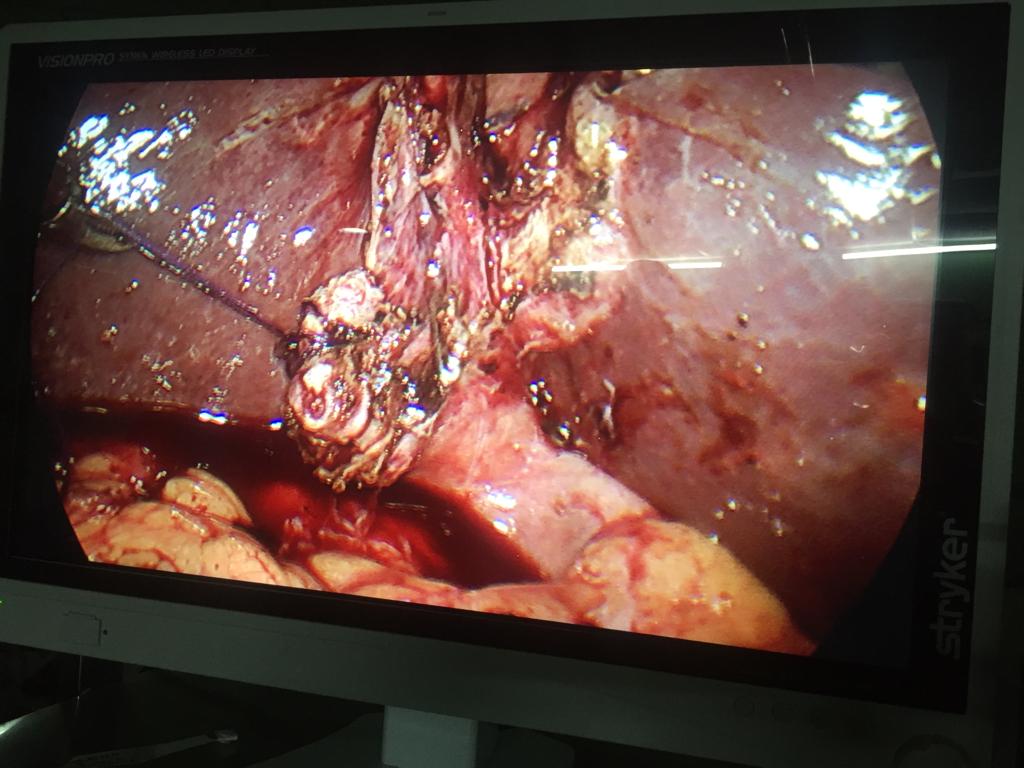

Difficult cases of appendicitis done completely laparoscopically